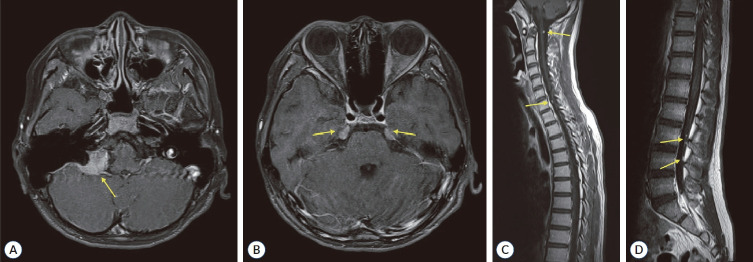

Schwannomatosis (SWN) is now recognized as a broad classification that includes neurofibromatosis (NF) type 2, reflecting their shared genetic and phenotypic characteristics. Previously, SWN and NF type 2 were considered distinct clinical entities; however, the 2022 classification revision has unified them under the umbrella of SWN, with NF type 2 now referred to as NF2-related SWN. SWN arises from mutations in NF2, SMARCB1 (SWI/SNF related, matrix associated, actin dependent regulator of chromatin, subfamily b, member 1) or LZTR1 (leucine zipper like transcription regulator 1). Recent diagnostic criteria for SWN incorporate molecular classification, including "NF2-related SWN", "SMARCB1-related SWN", "LZTR1-related SWN", "22q-related SWN", "SWN-not otherwise specified", or "SWN-not elsewhere classified". NF2-related SWN is a genetic condition where all individuals with a germline or constitutional NF2 mutation are destined to develop the disease. The pathogenesis of SMARCB1- or LZTR1-related SWN follows a three-step, four-hit model. This involves retention of the mutated germline SMARCB1 or LZTR1 allele in the tumor, loss of the wild-type chromosome 22, and somatic mutation in the NF2 gene. Clinically, NF2-related SWN involves bilateral vestibular schwannomas, with treatment options including microsurgery, radiotherapy, and bevacizumab, each with specific benefits and limitations. Patients with SWN frequently present with chronic pain caused by schwannomas, which often does not correlate with tumor size, location, or burden. Management of SWN is primarily symptom-based. Surgical intervention is reserved for symptomatic lesions, particularly in cases of spinal cord compression or significant functional impairments. Multidisciplinary approaches to pain management are critical for enhancing quality of life. Although malignant transformation of schwannomas is a potential risk, the life expectancy of individuals with SWN is nearly normal. Despite advancements in understanding SWN, further research is necessary to elucidate the underlying genetic mechanisms and to develop targeted therapeutic strategies for this complex disorder.